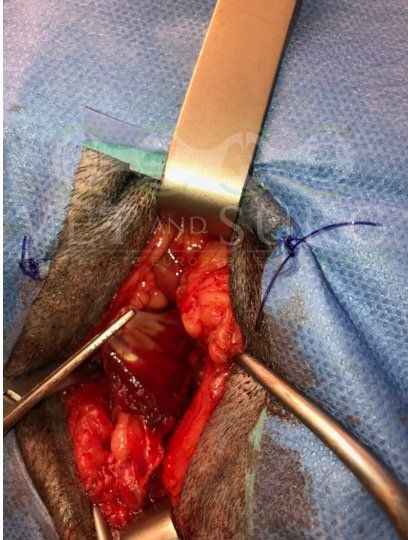

Obstruction urétérale chez un chat Sacré de birmanie de 8 ans

Une pose de SUB a été effectuée, reliant la cavité pyélique gauche à la vessie, en court-circuitant l'uretère obstrué.